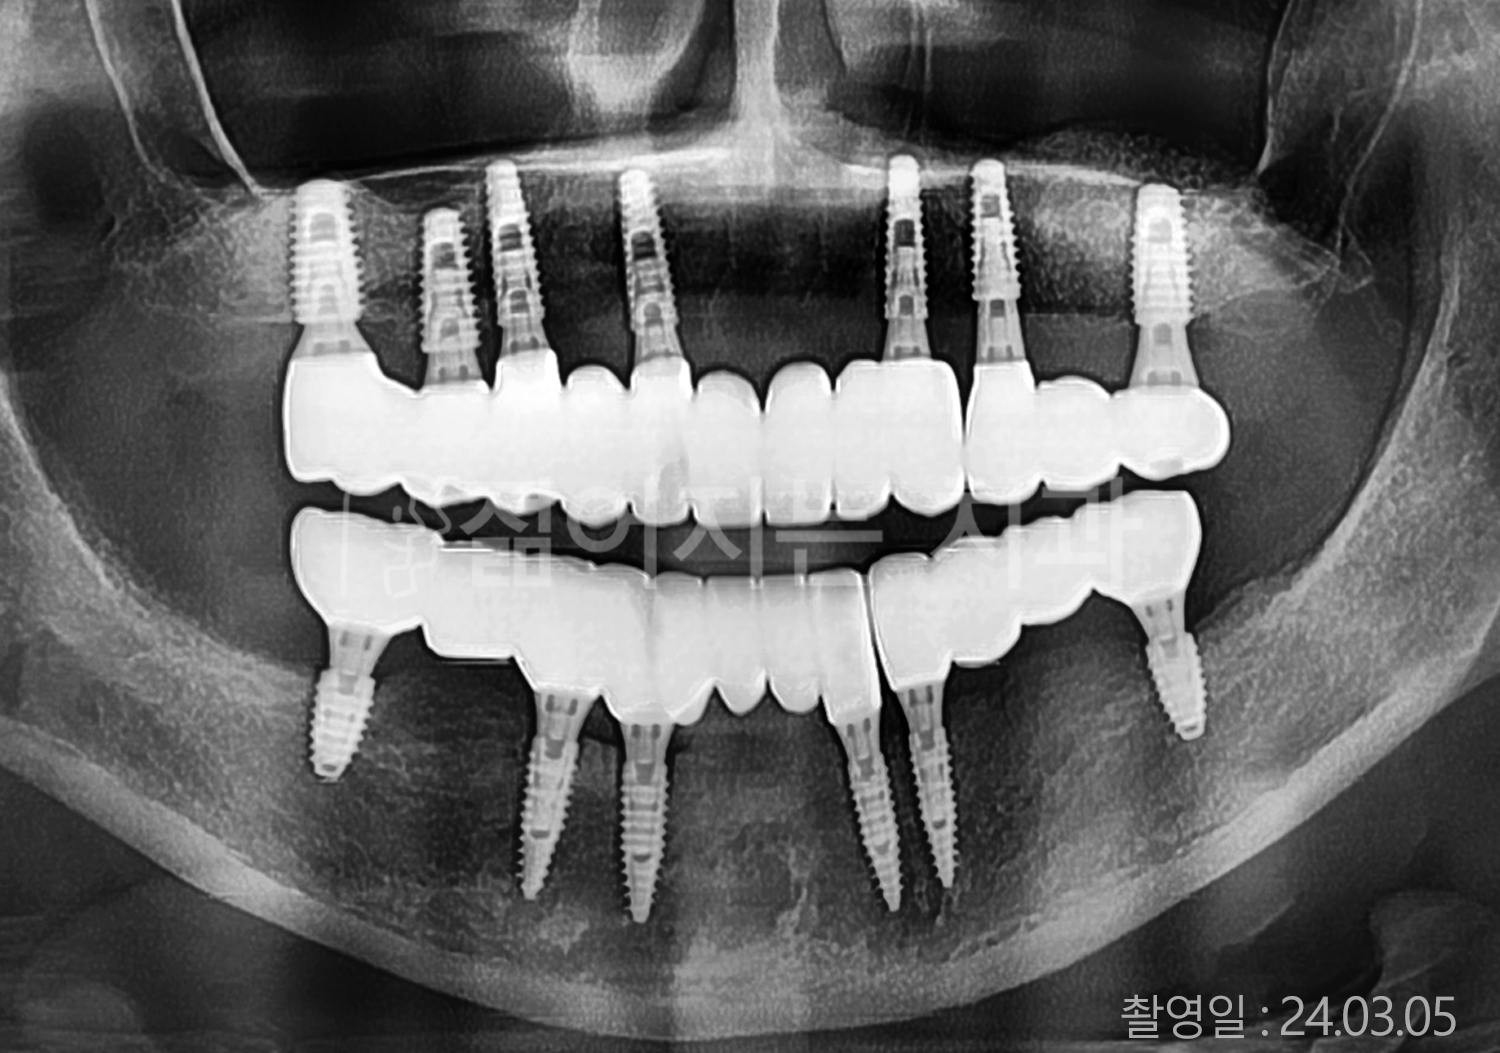

• 70대 고혈압, 당뇨 전체치아 10개 이상 임플란트

• 50대 고혈압, 당뇨 전체치아 10개 이상 임플란트

• 60대 고혈압, 당뇨 전체치아 10개 이상 임플란트

• 50대 전체치아 10개 이상 임플란트

• 70대 당뇨 전체치아 10개 이상 임플란트

• 80대 전체치아 10개 이상 임플란트

• 40대 전체치아 10개 이상 임플란트

• 60대 고협압, 고지혈증 전체치아 10개 이상 임플란트

• 60대 전체치아 10개 이상 임플란트

위 사진의 저작권은 젊어지는 치과에 있습니다.

* 위 사진은 동일 조건에서 촬영 되었습니다. / 모든 치료에는 부작용이 발생할 수 있습니다.